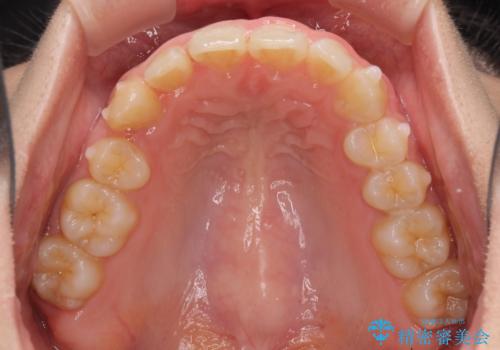

- 八重歯を気にして来院された患者様です。

八重歯の後ろの歯を1歯抜歯し、補助装置(リンガルアーチ)を用いて八重歯の位置を改善し、その後インビザラインにより矯正治療を行うこととしました。

下顎前歯が1本欠損したスリーインサイザーという状態であるため、上下の前歯の咬み込みが深くなったり、奥歯の咬み合わせが理想的なものとならなかったりという仕上がりになってしまいます。

前歯の見た目や奥歯の咬み合わせに、患者様が違和感を感じない状態として治療を終えました。